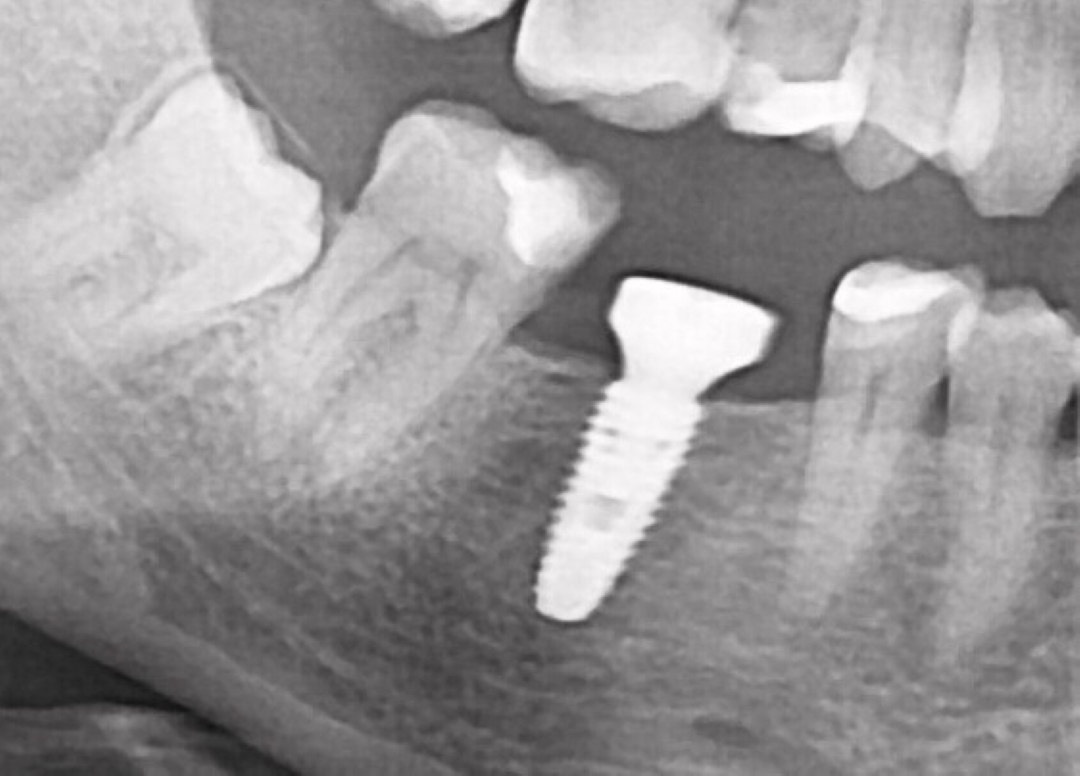

Ранее удаленный зуб 36 - незначительная атрофия по костным тканям и довольно выраженная атрофия по мягким тканям.

Имплант Straumann BLT 4.1*8mm SLActive - установлен в субкрестальное положение, произведено профилирование кортикальной кости системой Straumann Bone Profiler с целью создания более выгодного профиля прорезывания и исключения костной резорбции в области шейки импланта.

Чтобы компенсировать недостаточный объем мягких тканей проведена - мягкотканая пластика деэпителизированным соединительнотканным трансплантантом с неба.

Установлен заживляющий абатмент диаметром 6.5 мм.

Обратите внимание на объем и качество мягких тканей в области будущей финальной реставрации!

Финальная реставрация и диоксид циркония в полную анатомию методом раскрашивания.

Резюме:

Этот кейс мы с Сергеем смело относим к разряду простых - но, если посмотреть на него внимательно - здесь на каждом этапе есть определенные нюансы начиная от разреза и заканчивая финальной реставрацией.